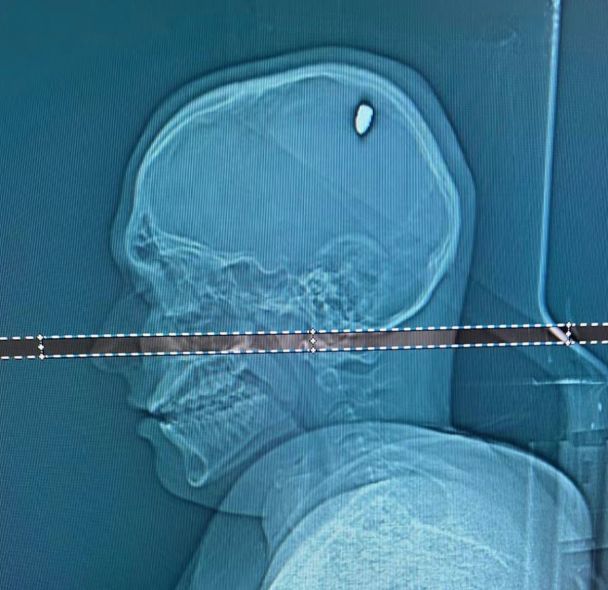

Нейрохірург Флавіо Фалькомета, який оперував Матеуса, сказав: "Частина кулі пробила його мозок, що спричинило стиснення в цій зоні і призвело до мимовільних рухів його руки. Якби вона опинилася за декілька міліметрів від того місця, де зупинилася, це могло б спричинити набагато серйозніші пошкодження, внаслідок чого його рука чи одна сторона тіла була б паралізована".